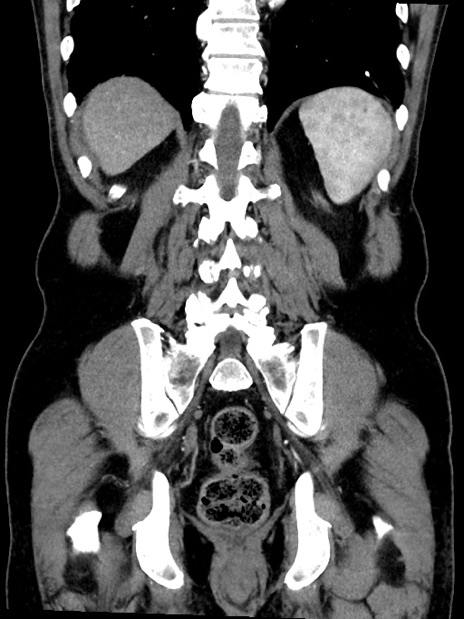

症例35(冠状断像)

【症例】70歳代 男性

【主訴】腹部膨満、嘔吐

【現病歴】昨日より腹部膨満感出現。本日増悪し、仙痛出現。嘔吐あり、受診。

【既往歴】糖尿病、胆摘後

【身体所見】BP 149/80mmHg、HR 74/min、BT 35.9℃、腹部:膨満、軟、圧痛なし。腸雑音減弱あり。上腹部正中切開瘢痕あり。

【データ】WBC 13500、CRP 1.72